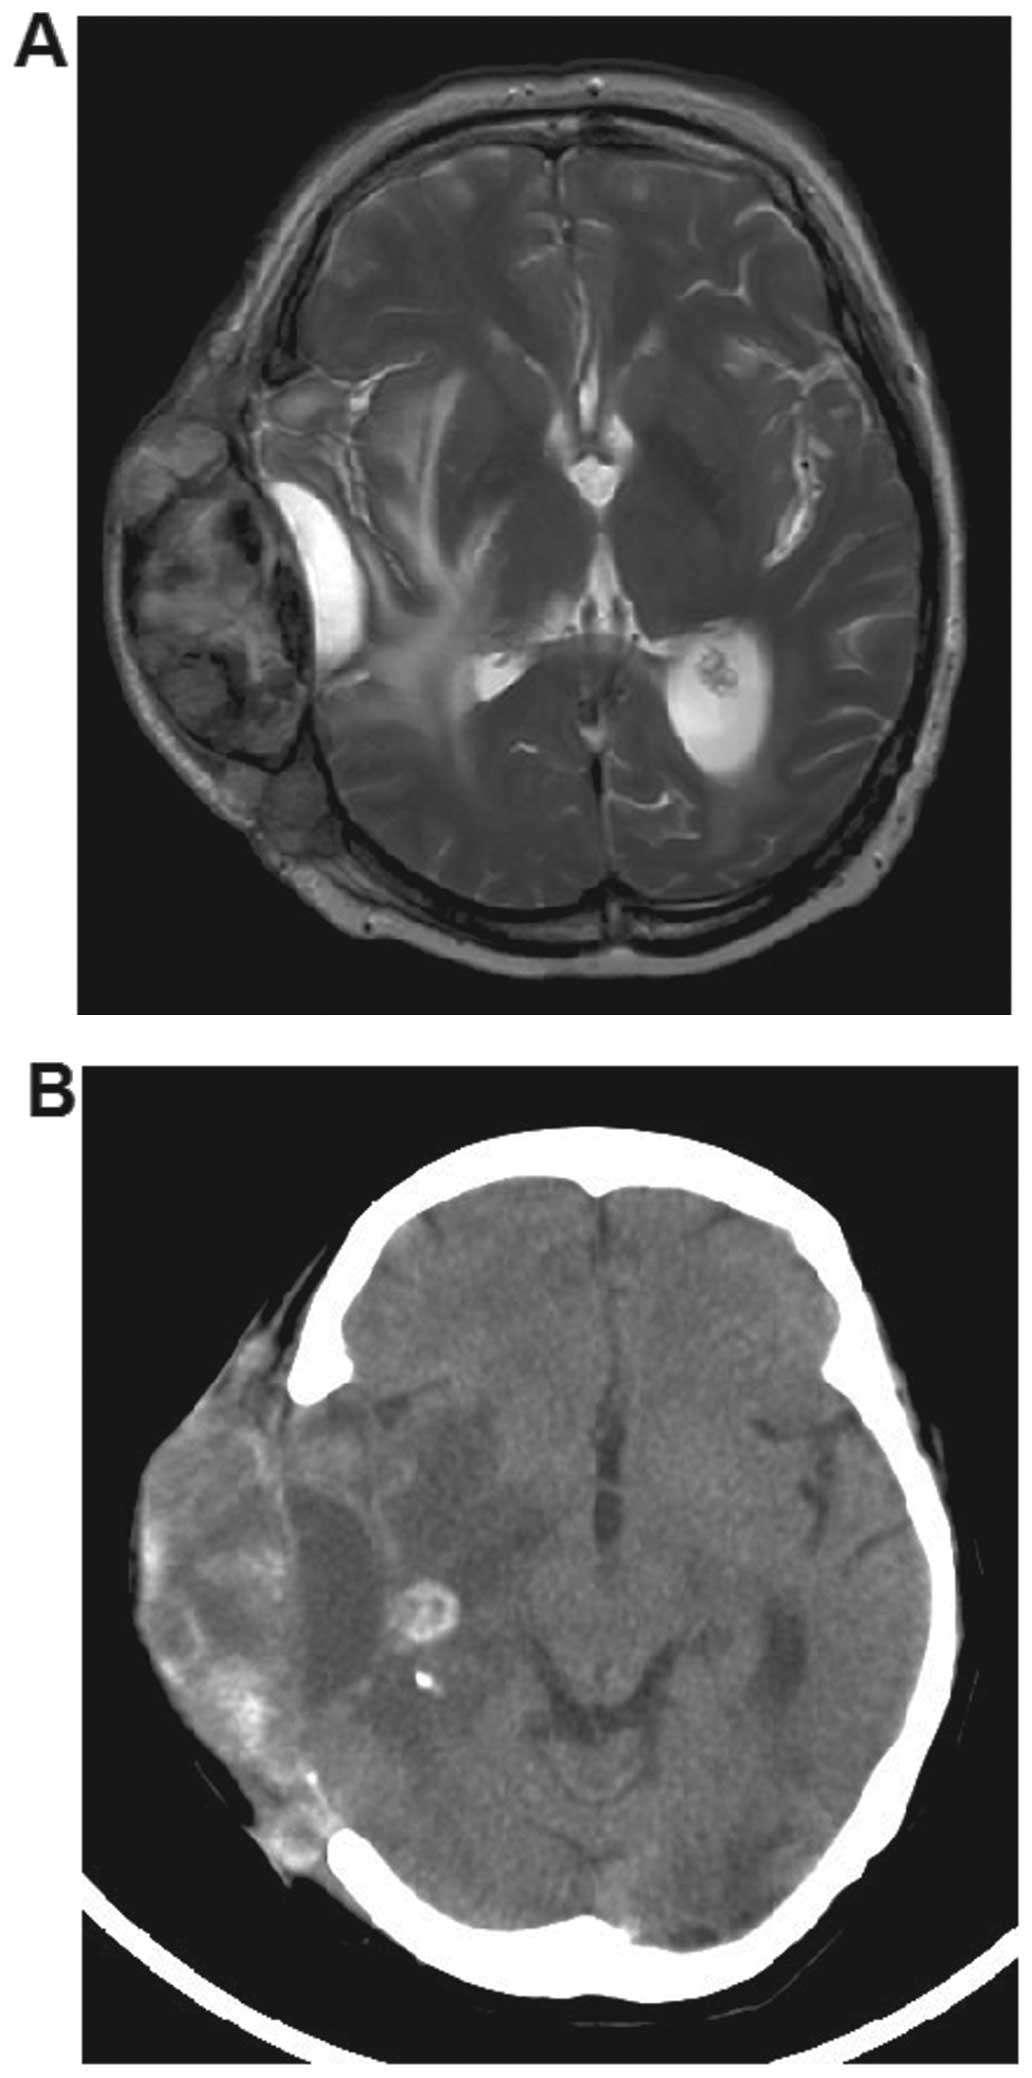

• Subcutaneous Metastasis After Three Surgeries For Brain ... , Melanoma Is A Malignancy Of.

Subcutaneous Melanoma , Subcutaneous Metastasis After Three Surgeries For Brain ...